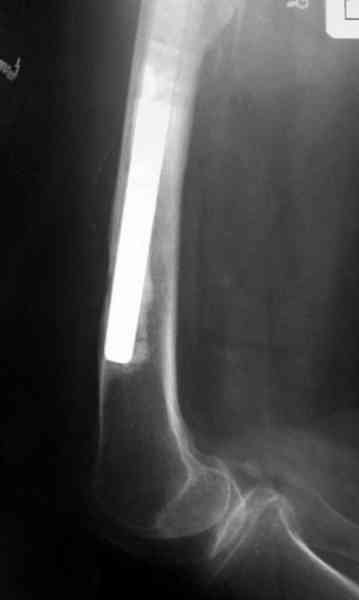

Приглашенный хирург установил ревизионный вариант бедренного компонента без замены ацетабулярного компонента, что осложнилось нагноением и свищами на уровне сустава и средней трети бедра. После двухгодичного безуспешного лечения перевязками и антибиотиками больная обратилась к нам на консультацию.

Для спейсера в бедро использовал старый длинный бедренний компонент меньшего диаметра, облепленный со всех сторон цементом с антибиотиком.

№3-6 снимки с осложнением